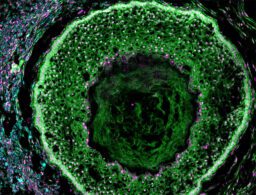

![]() | Ovarian Organoids to Study Reproductive HealthMedgadget - (Tuesday February 28, 2023) - Daily Reads / Medgadget | |||